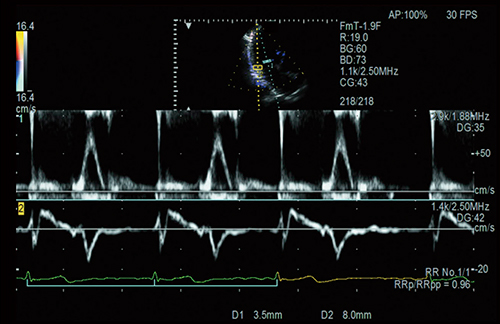

心エコーにおける血行動態指標のうち,僧帽弁口血流速波形の拡張早期波形E波やE波と僧帽弁輪部の拡張早期波形e’波の比であるE/e’は充満圧の指標であり,心不全診断に有用と言われている2)。当社では,Dual Gate Doppler機能を利用することにより,わずか5秒でE/e’を計測することが可能である。Dual Gate Dopplerは,任意の2か所のドプラ波形を同時に観察することが可能であり(図1),自動的に左室流入路および僧帽弁輪の位置にそれぞれサンプルゲートを設定し,同一心拍でE/e’を計測することが可能である。心不全に関連する心房細動,不整脈のような不規則な心拍の場合には,先々行R-R間隔と先行R-R間隔の比が1に近い区間が計測に適している3),4)。“R-R Navigation機能”は,計測に適した区間を自動で検出し表示することが可能であり,Dual Gate Dopplerと併用することで,拡張機能評価において最も安定した心拍で,再現性の高い計測が可能となり,臨床現場での有用性が期待されている5)〜8)。

また,ASE/EACVIガイドライン9)では,E波とe’波の拡張の開始時間の差(TE-e’)を計測することを推奨している。健常例では,e’波の方がE波よりも早く開始するのに対し,心不全の進行に伴いe’波の開始が遅れ,左房圧の上昇を評価できると報告されている。さらに,TE-e’から肺動脈楔入圧(PAWP)>12mmHgを予測できることが報告されている7)。図2は,経カテーテル大動脈弁留置術(以下,TAVI)前後における拡張のタイミングのズレだが,TAVI前後で僧帽弁口血流速波形には変化がないが,左房圧の減少に伴いTE-e’がTAVI後に短縮することが一目でわかる。TE-e’から左室充満圧と左室弛緩のバランスを加味した拡張機能の評価が可能であり,正確な時間差を計測するためにはDual Gate Dopplerが必要である。

図1 任意の2か所のドプラ波形を同時観察可能なDual Gate Doppler

図2 TAVI前後におけるE波とe’波の時間差(TE-e’)

(画像ご提供:筑波大学医学医療系循環器内科学臨床検査医学教授・石津智子先生)